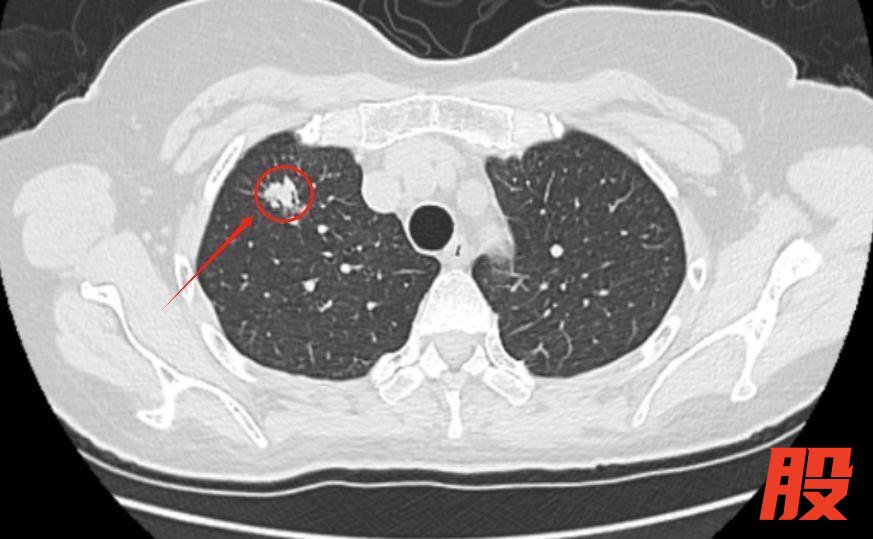

“我母亲从不吸烟,怎么会查出肺癌?”近日,63岁刘阿姨(化名)的儿女拿着母亲的诊断报告,满是困惑与不解。平素身体健朗的刘阿姨,无吸烟史、无慢性呼吸道疾病史,却在年度体检中意外发现右上肺直径约1.2cm的磨玻璃结节。随后,儿女陪同她前往湖南省第二人民医院(湖南省脑科医院)微创中心胸外科就诊。

接诊的舒升光主任医师结合刘阿姨的影像学特征与病史,迅速邀请呼吸内科、放射科、病理科开展多学科会诊(MDT),经全面评估后,为其制定了胸腔镜下肺结节微创切除方案。近日,手术在全麻下顺利完成,术中快速病理提示腺癌,术后病理确诊为肺腺癌IA2期。得益于早期发现与规范治疗,刘阿姨的病情得到了有效控制。